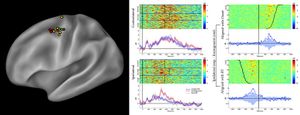

- 3.43 Functional Mapping of the Human Visual Cortex with Intravoxel Incoherent Motion MRI

Publication: PLoS One. 2015 Oct 7;10(10):e0139434. PMID: 26444010 | PDF Authors: Tax CM, Chamberland M, van Stralen M, Viergever MA, Whittingstall K, Fortin D, Descoteaux M, Leemans A. Institution: Image Sciences Institute, University Medical Center Utrecht, Utrecht, The Netherlands. Background/Purpose: Fiber tractography plays an important role in exploring the architectural organization of fiber trajectories, both in fundamental neuroscience and in clinical applications. With the advent of diffusion MRI (dMRI) approaches that can also model "crossing fibers", the complexity of the fiber network as reconstructed with tractography has increased tremendously. Many pathways interdigitate and overlap, which hampers an unequivocal 3D visualization of the network and impedes an efficient study of its organization. We propose a novel fiber tractography visualization approach that interactively and selectively adapts the transparency rendering of fiber trajectories as a function of their orientation to enhance the visibility of the spatial context. More specifically, pathways that are oriented (locally or globally) along a user-specified opacity axis can be made more transparent or opaque. This substantially improves the 3D visualization of the fiber network and the exploration of tissue configurations that would otherwise be largely covered by other pathways. We present examples of fiber bundle extraction and neurosurgical planning cases where the added benefit of our new visualization scheme is demonstrated over conventional fiber visualization approaches. Funding:

|